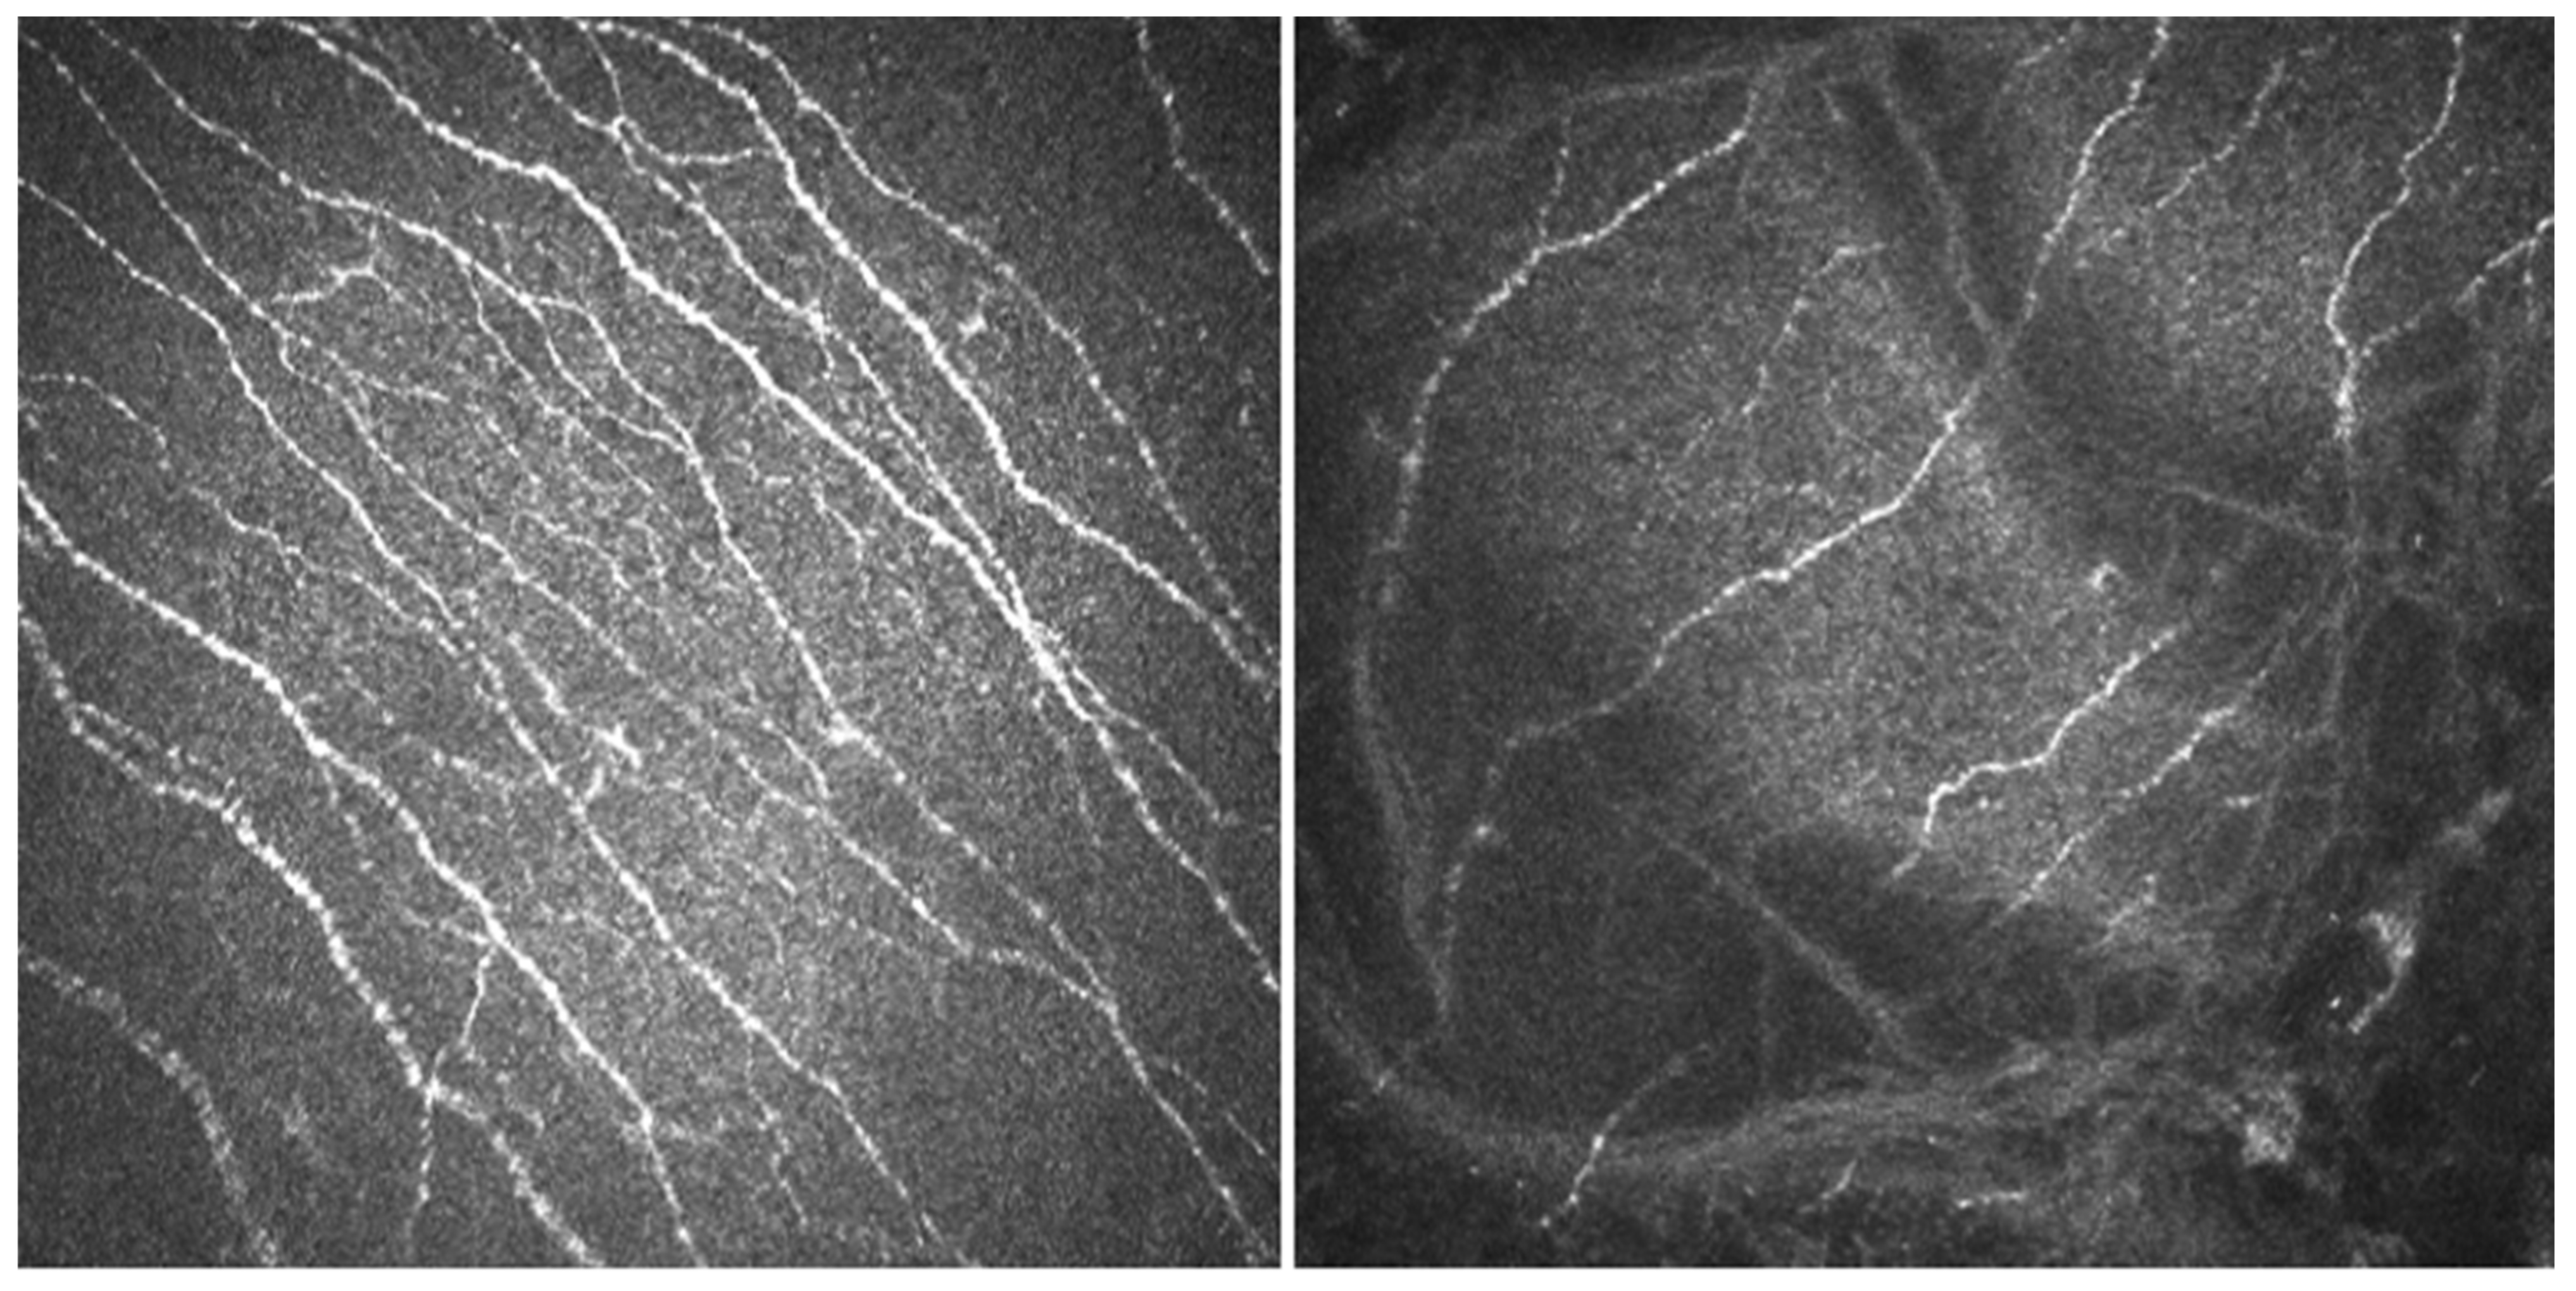

- In vivo confocal microscopy (IVCM). Laser scanning IVCM of the cornea was performed using the Rostock cornea module of the Heidelberg Retina Tomograph 3 (Heidelberg Engineering GmbH, Heidelberg, Germany). Before examination, a drop of anesthetic was instilled, and an eye speculum was used to keep the lids wide open. A drop of Viscotears Gel (Carbomer 980, 0.2%; Novartis Farmacéutica S.A., Barcelona, Spain) was deposited on the objective lens, thus avoiding direct contact of the TomoCap with the cornea. At least three good quality, non-overlapping images from the sub-basal nerve plexus of the central cornea were obtained using sequence and/or volume scans, and were used for the analysis. Each image was comprised of 384 × 384 pixels covering an area of 400 × 400 μM (0.16 mm2) with a transverse optical resolution of 2 μM, an axial optical resolution of 4 μM, and an acquisition time of 0.024 s.For IVCM image analysis, two masked observers analyzed the following in the three images: (1) nerve morphology parameters of density, length, branching density, and grade of tortuosity; (2) density of dendritic cells; (3) presence of neuromas; and (4) reflectivity from the confocal images, as an index of optic densitometry or transparency of cornea [14]. The mean value between the two observers for each parameter was computed for statistical analysis.Nerve density (n/mm2) and length (mm/mm2) were measured using the plugin NeuronJ (http://www.imagescience.org/meijering/software/neuronj/ accessed on 25 May 2021) from the ImageJ and provides quantification. The number of nerve branch points and dendritic cells (identified in the sub-basal nerve plexus by their distinctive features, i.e., bright cell bodies with dendritic form structures), were manually determined using the multipoint tool of the ImageJ software, and the densities calculated (n/mm2) as described in a previous study [15]. The grade of nerve tortuosity was evaluated according to the scale (0–4) reported by Oliveira-Soto and Efron [16] for main nerves. The histogram of each image based on the ImageJ plugin was used to obtain the mean reflectivity or optic densitometry [14]. These parameters were compared with well-established values for normal corneas and performed with the same type of confocal microscope. Specifically, we used data from Giannacare et al. [17] for nerve length, and from our group for nerve density, density of nerve branches, density of dendritic cells, [15] and nerve tortuosity and reflectivity [14].